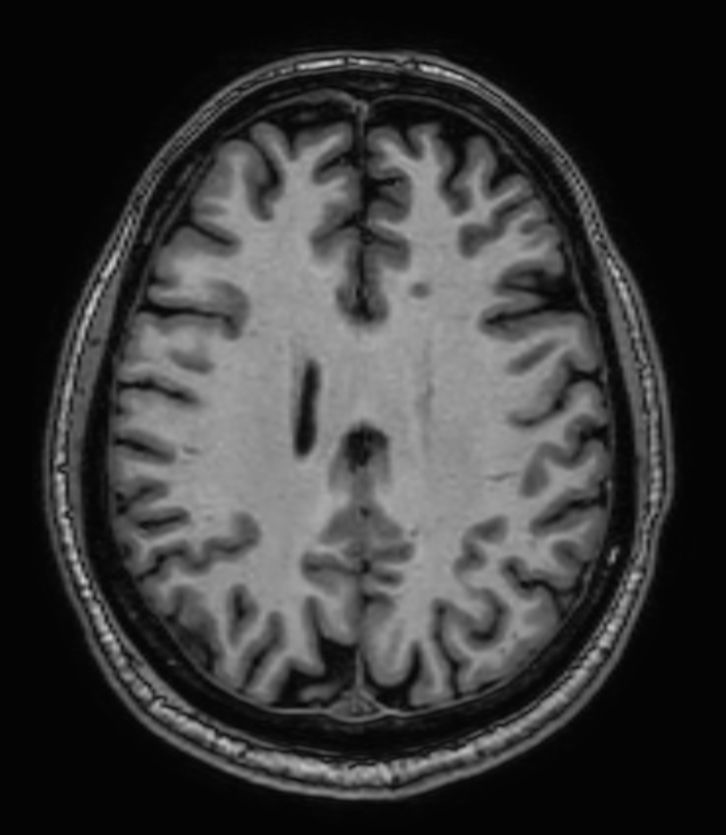

3D T1w FFE Compressed SENSE

3D T1w FFE (Reformat) Compressed SENSE